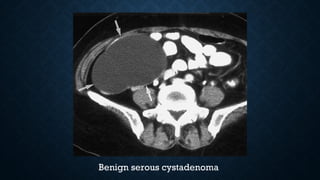

Benign serous cystadenoma